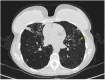

Non-tuberculous mycobacteria (NTM) are ubiquitous environmental organisms that may cause opportunistic infections in susceptible hosts. Lung infections in immunocompetent persons with structural lung disease are most common, while disseminated disease occurs primarily in immunocompromised individuals. Human disease caused by certain species, such as Mycobacterium avium complex, Mycobacterium abscessus, and Mycobacterium kansasii, is increasing in incidence and varies by geographic distribution. The spectrum of NTM disease varies widely in presentation and clinical outcome, but certain patterns can be organized into clinical phenotypes. Treatment options are limited, lengthy, and often toxic. The purpose of this case-based review is to provide non-clinician scientists with a better understanding of human NTM disease with an aim to stimulate more research and development.